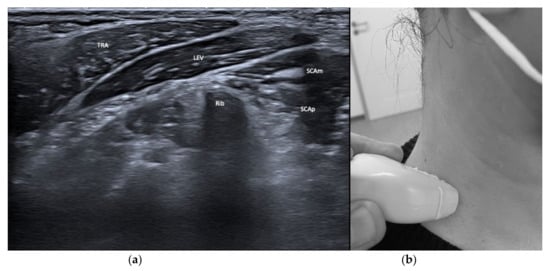

| Splenius cervicis (SPLcer) | Ipsiversion of neck | +++ | ++ | LEV, TRA, Longissimus cervicis | Relevant for full turn of the neck |

| Ipsitilt of the neck | |||||

| Levator scapulae (LEV) | Lift of scapula | + | + | SPLcer, TRA | |

| Ipsitilt of head and neck | Role for antecollis variants is discussed variably | ||||